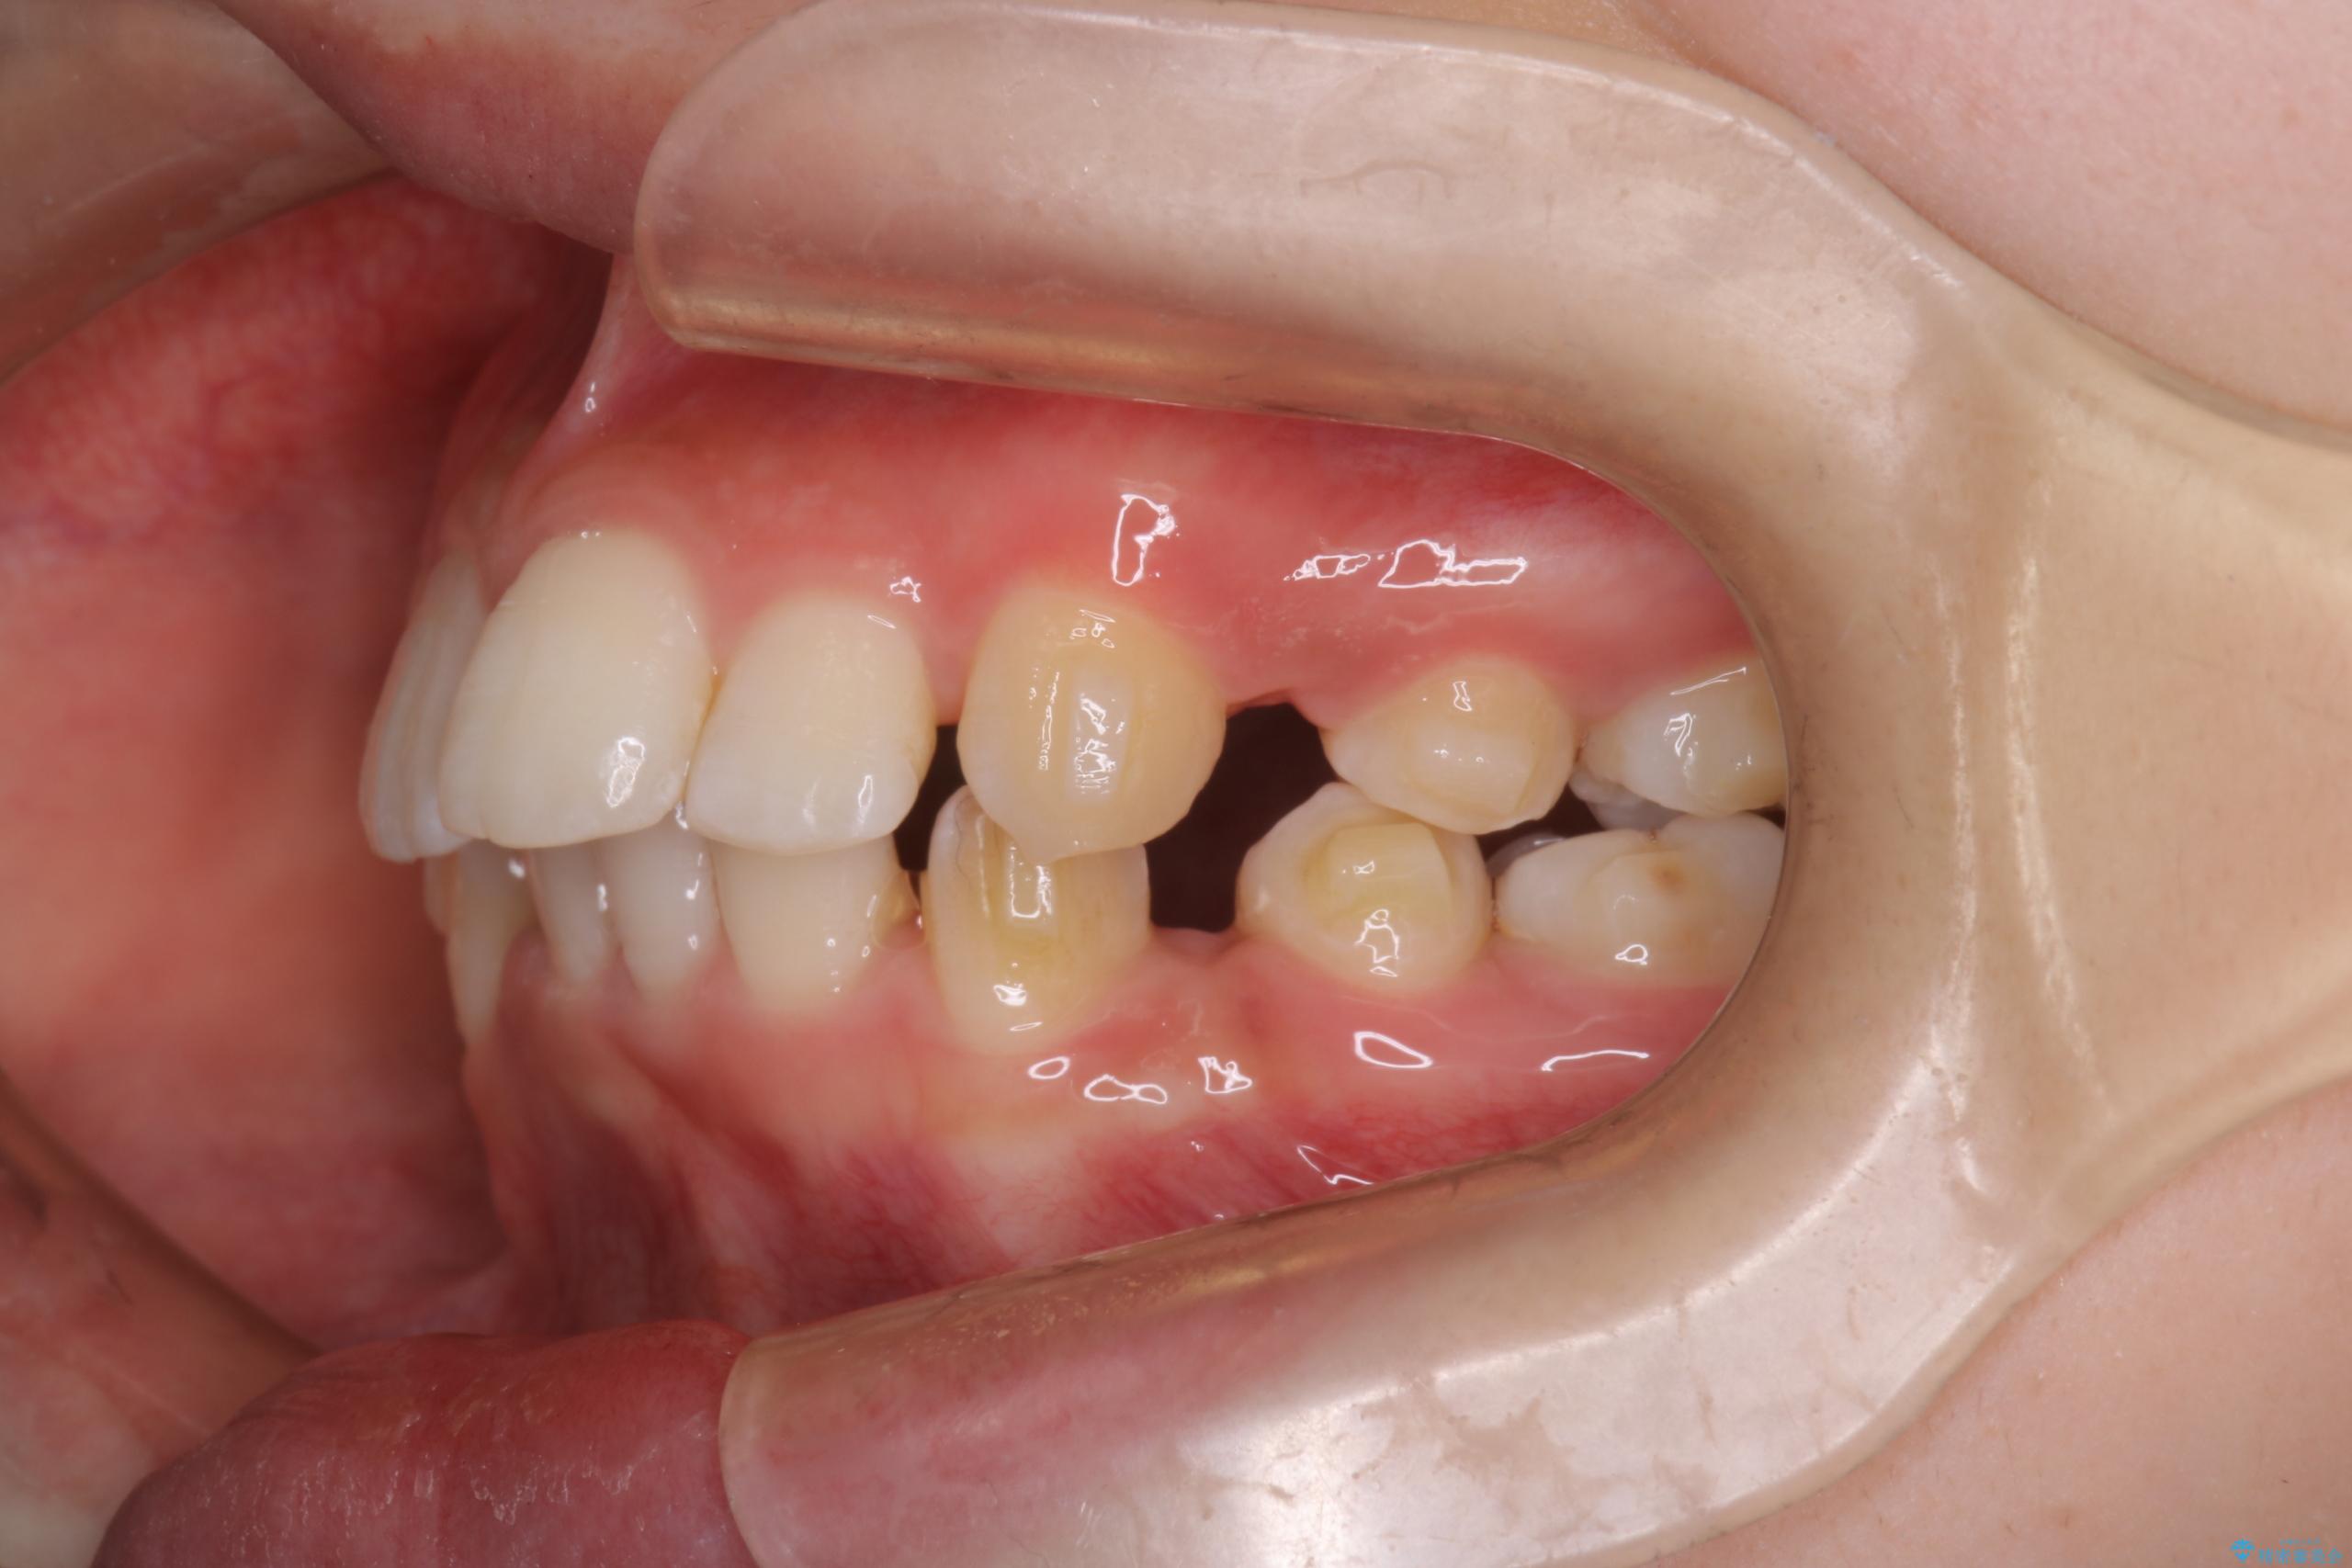

- 前歯から奥歯にかけて歯の重なりが激しい歯のがたつき(重度叢生)を主訴にご来院されました。精密検査の結果、歯が並ぶスペースが大幅に不足しており、歯並びを整え、口元を美しく引っ込めるためには、スペースの確保が必要と診断しました。そこで、上下左右の第一小臼歯(4番目の歯)を計4本抜歯し、そのスペースを利用して歯並び全体を整える抜歯矯正の治療計画を立案。装置には、透明で目立たないインビザラインを採用し、審美性と治療効果の両立を目指しました。

今回の治療では、重度の叢生を改善するため、まず計画通り上下左右4本の小臼歯を抜歯し、歯を並べるための十分なスペースを確保しました。装置には透明で取り外し可能なインビザラインを使用。抜歯によってできたスペースを最大限に活用し、マウスピースを定期的に交換しながら、デコボコを解消しつつ、前歯を効果的に後退させました。

治療の結果、長年の悩みであった重度の歯のがたつきが解消され、口元の突出感も改善。機能的にも安定し、審美的にも美しい、理想的な歯並びを獲得していただけました。